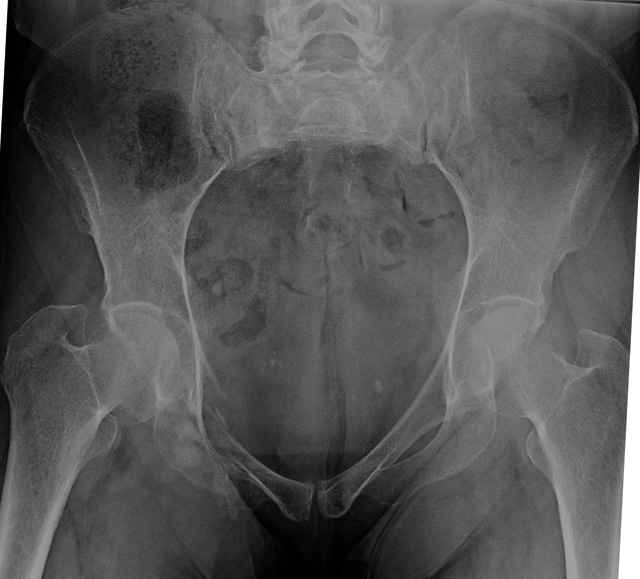

3 Months After Fall

Continued Pain & Immobility

(+) Instability to Compressive Manual Exam

Pelvic CT Scan - 3 Months After Fall

Sacral Injuries

Ramus Fractures

Percutaneous Fixation

(B) Ramus-Retrograde

2 TransIliac-TransSacral

Upper Segment